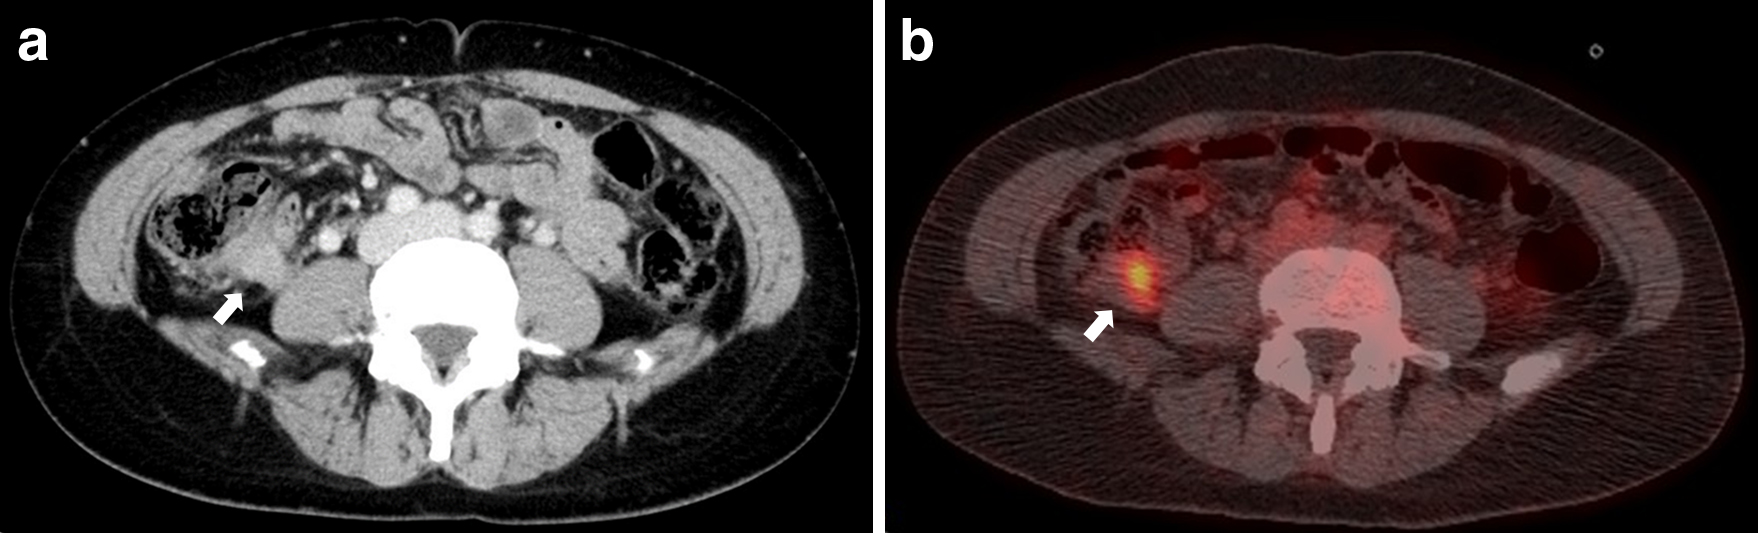

腹部造影CT所見:虫垂根部に造影効果を伴う20 mm大の腫瘤を認めた(Fig. 1a).

FDG-PET/CT所見:虫垂根部の腫瘤にSUVmax=5.39の集積を認めた.その他の部位に明らかな異常集積を認めなかった(Fig. 1b).